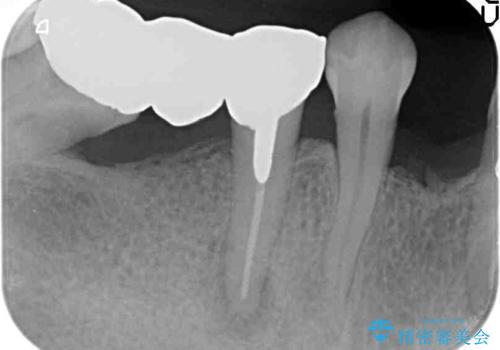

検査の結果、感染根管や欠損、歯周病により残すことのできない歯、等多々問題が認められます。

残すことのできる歯できない歯を選別し、欠損部にはインプラントによる咬合機能の回復、保存できる歯には歯周病治療・根管治療を行う治療計画としました。